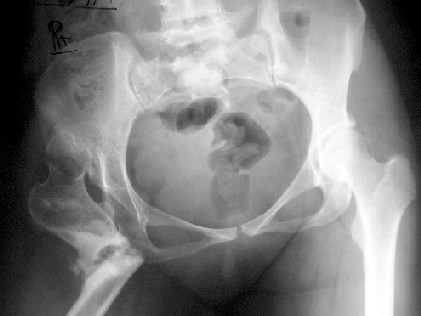

A 30-year-old female patient, presented with pain and limping post hip surgery and lengthening using Ilizarov technique 2 years duration.She said she had only limping preop. now she has painful limping and she can't walk without using walking aid.

Her X-ray --> non-union at the osteotomy site,pelvic tilt,bowing of the femur.clinically painful mobile pseudoarthrosis, LLD =4CM. Could those colleagues using such type of osteotomy Ilizarov method give us the clues how to treat such problems?Does this type of osteotomy still practiced by the group?Dr.Freih Odeh Abu Hassan,M.D(Orth.), F.R.C.S(Eng.), F.R.C.S.(Tr.&Orth.),Asst.Professor of Orthopedics Surgery,Jordan University - Amman.

Лично мне не очень понятно, по поводу чего производилось лечение методом Илизарова. И происхождение подвздошного вывиха - тоже.

Это вариант лечения по Илизарову при врожденном вывихе бедра у взрослых. Основан на методе Шанца (создание упора под впадину - вот как раз где не срослось), дополненный удлинением дистально с восстановлением механической оси бедра.

Если бы данная пациентка находилась у нас в клинике, то, очевидно, была бы выполнена костная аутопластика зоны ложного сустава, компенсация укорочения за счет формирования дистракционного регенерата в с/3-н/3 сегмента. Однако, это "в общем" и если лечить рентгенограмму. Необходимо иметь дополнительную информацию о стойкости перекоса таза, статусе позвоночника, "остатках"

механической оси конечности, функции коленного сустава, мышечном окружении и т.п. В случае, если уважаемый коллега Dr.Freih Odeh Abu Hassan не имеет опыта реконструктивных операций этой области, убежден, что больную целесообразно направить в специализированный центр. Оперативное лечение могло бы быть выполнено и в стенах РосНИИТО им. Р.Р.Вредена.

This operation - the Ilizarov Hip Reconstruction consists of an extreme valgus osteotomy in the proximal femur, to stabilise the unstable hip, a lengthening distally to equalise the limb lengths, and a varusization thru that lengthening zone to bring back the distal limb parallel to the other limb, and normalise the "mechanical axis".